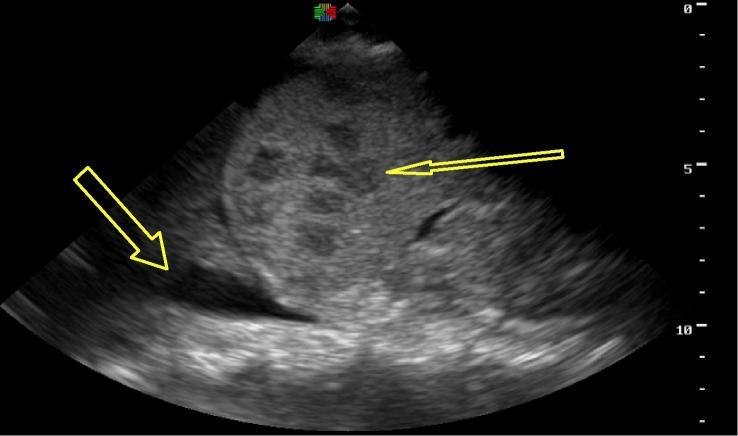

The majority of HIV-TB co-infection worldwide is reported in Africa. The risk of developing extra-pulmonary tuberculosis (EPTB) increases as immune deficiency progresses but is difficult to diagnose. Point-of-care ultrasonography (POCUS) can be an effective adjunct to identify and treat EPTB-associated findings using the focused assessment with sonography for HIV-associated TB (FASH) protocol.

Three HIV-infected patients without known history of EPTB presented to a Rwandan district hospital with fever and unclear infection. Initial testing did not reveal a source. Each patient was then evaluated with the FASH protocol by a Rwandan emergency physician with POCUS training. All patients had findings suggestive of EPTB by ultrasound. Anti-TB treatment was initiated, and all subsequently demonstrated symptom improvement.

据报告,全球大多数艾滋病毒与结核病合并感染病例发生在非洲。随着免疫缺陷的进展,发生肺外结核病(EPTB)的风险会增加,但这种疾病很难诊断。即时超声检查(POCUS)可以作为一种有效的辅助手段,使用针对艾滋病毒相关结核病的超声重点评估(FASH)方案来识别和治疗与EPTB相关的病症。

三名无EPTB病史的艾滋病毒感染患者因发热和感染情况不明前往卢旺达一家地区医院就诊。初步检查未发现感染源。随后,一名接受过POCUS培训的卢旺达急诊医生采用FASH方案对每名患者进行了评估。所有患者的超声检查结果均提示患有EPTB。于是启动了抗结核治疗,所有患者随后症状均有所改善。